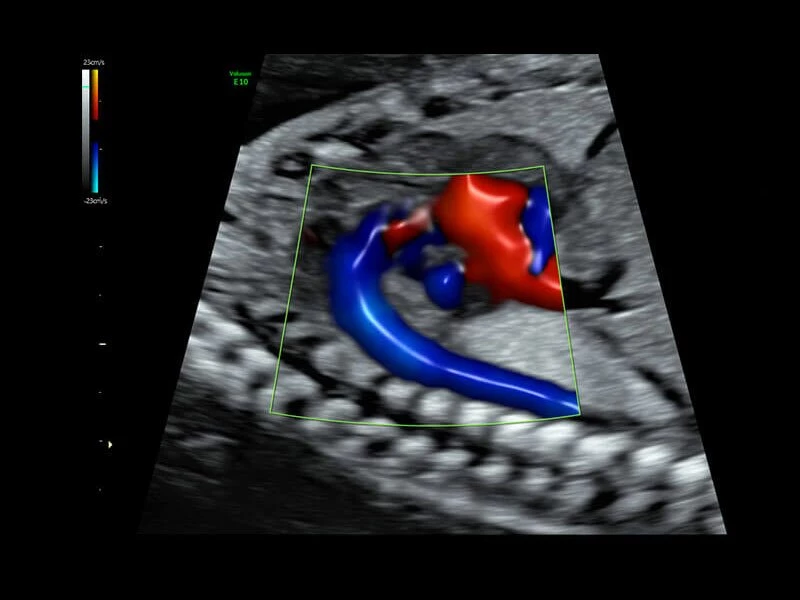

Она оснащена инструментами, которые упрощают получение изображений, отличается высокой чувствительностью цветового допплера, поддерживает инновационные 3D/4D технологии.

Voluson E10 поддерживает инновационные технологии формирования изображений — HDlive Silhouette и HDlive Flow, которые позволяют увидеть мельчайшие детали. Алгоритм SonoRenderlive упрощает рабочий процесс и дает возможность реконструировать изображение поверхностей, определяя область перехода между тканью и жидкостью.

- Технология HDlive Flow — повышает реалистичность визуализации сосудистых структур, улучшая восприятие глубины (по сравнению с традиционным цветовым допплером и функцией HD-Flow).

- HD-flow или, так называемый, высокочувствительный тканевый допплер.

- Позволяющая визуализировать плод в объеме стандартная программа HD-live с дополнительным приложением Hdlive Silhouette, включающим в себя режим «Силуэт», с помощью которого можно выделять границы тканей, контуры объектов. В этот же пакет входит и режим HDlive Flow, представляющий из себя источник света, перемещаемый и совместимый с режимом визуализации тока крови в объеме.

- Возможность визуализации тока крови в B-Flow (недопплеровский режим).